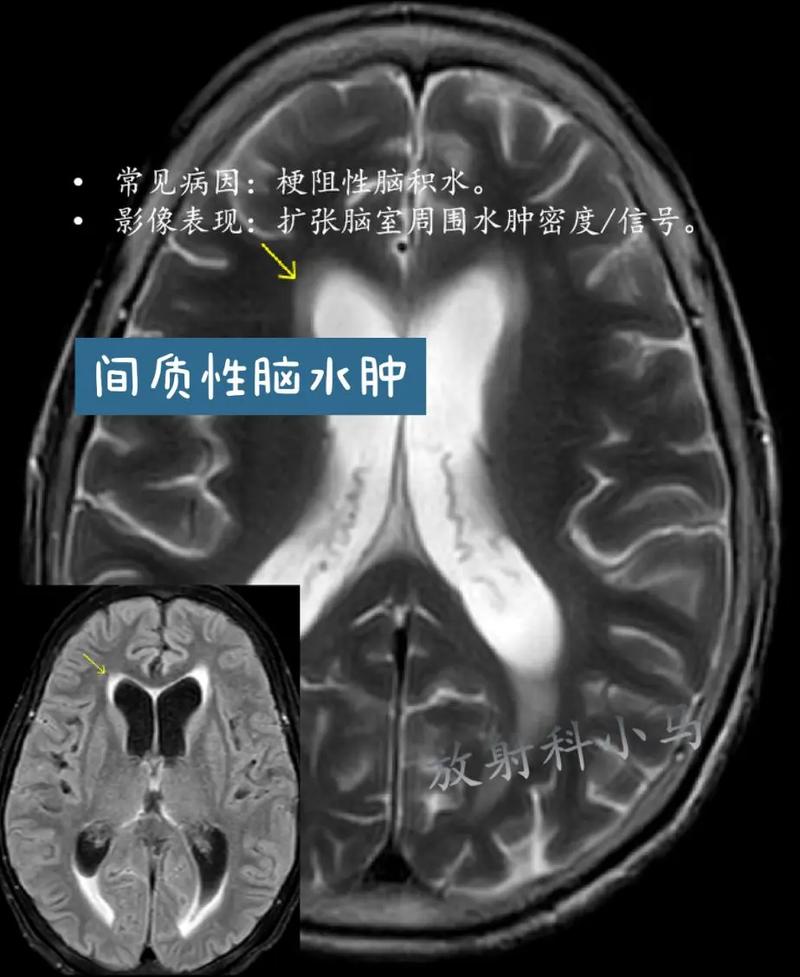

脑积水是由于脑脊液循环通路发生阻塞,导致脑脊液在脑室系统内过多积聚,使脑室扩大,从而压迫周围正常的脑组织,脑积水的症状发展通常比较缓慢,呈进行性加重,但急性脑积水(如脑出血后突然阻塞)则发展迅速。

脑积水的症状主要与颅内压增高和脑组织受压有关,具体表现因发病年龄和病情急缓而异。